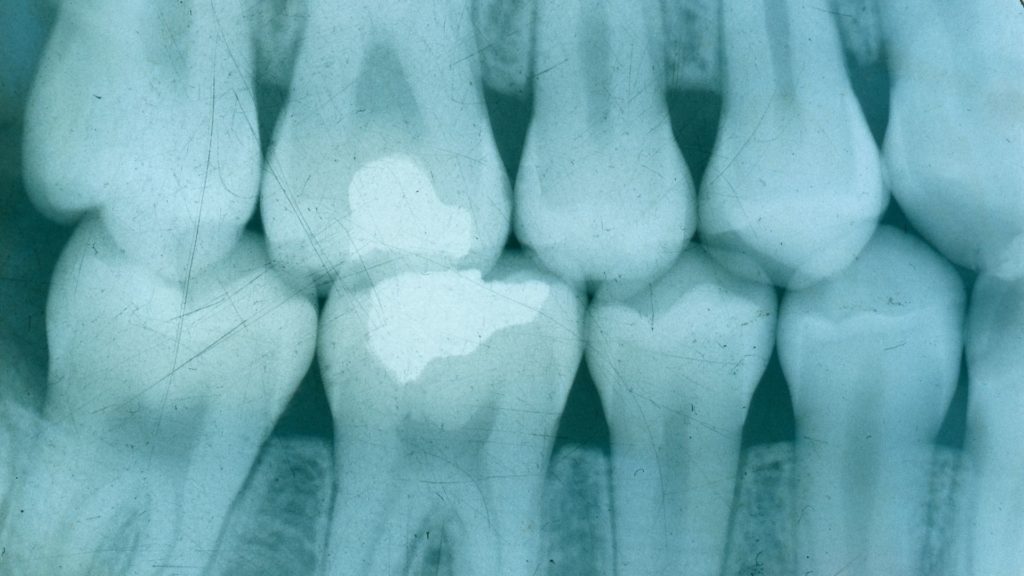

Bitewing (interproximal) X-ray

- This X-ray is similar in size to a periapical X-ray but uses a different technique. It focuses on the crown area of the teeth and is ideal for:

- Detecting cavities between teeth that are hard to see during a clinical exam

- Evaluating the health of supporting structures such as gums and bone